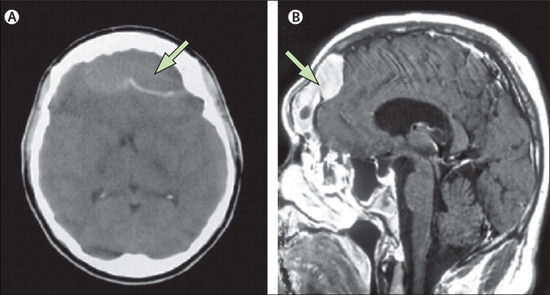

경막외농양 MRI영상경막외농양의 증상이 애매모호함에 따라 전두동염과 유사하기 때문에 앞이마의 통증과 발열이 계속된다면 의심해 보아야 합니다.농양이 커지면 뇌압이 상승하여 국소 운동 장애, 감각 장애, 발작을 볼 수 있습니다.CT, MRI를 통해 진단하고 추천이 필요한 사람 중에는 정상인 경우가 많습니다.